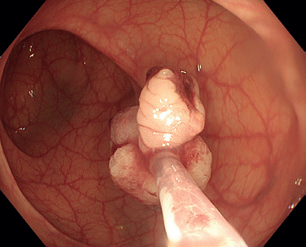

Obr. 5 Extrakce resekátu stopkatého polypu.EMR zahrnuje několik technik. Nejběžnější je technika „lift and cut“, při které se provádí submukózní injekce různých roztoků vedoucí ke zvednutí léze s následným uchopením a odstraněním kličkou (obr. 8–11). Submukózní injekce může obsahovat fyziologický roztok, glukózu a glycerol, zředěný adrenalin nebo gelatinózní látky. Pro lepší orientaci v submukóze se do roztoku často přidává modré barvivo, jako je methylenová modř nebo indigokarmín. Zvednutí léze dané rozšířením submukózy se označuje jako „lifting.“ V případě fibrózy nebo hluboké nádorové invaze dochází k „liftingu” jen částečně nebo vůbec, odstranění léze je poté obtížné až nemožné.

Obr. 7 Nakládání polypektomické kličky na lézi po submukózní injekci poblíž orificia appendixu.Relativně novou a perspektivní možností je EMR pod vodou („underwater”), což zahrnuje naplnění střevního lumen vodou a následnou resekci nařasené léze bez nutnosti submukózní injekce.